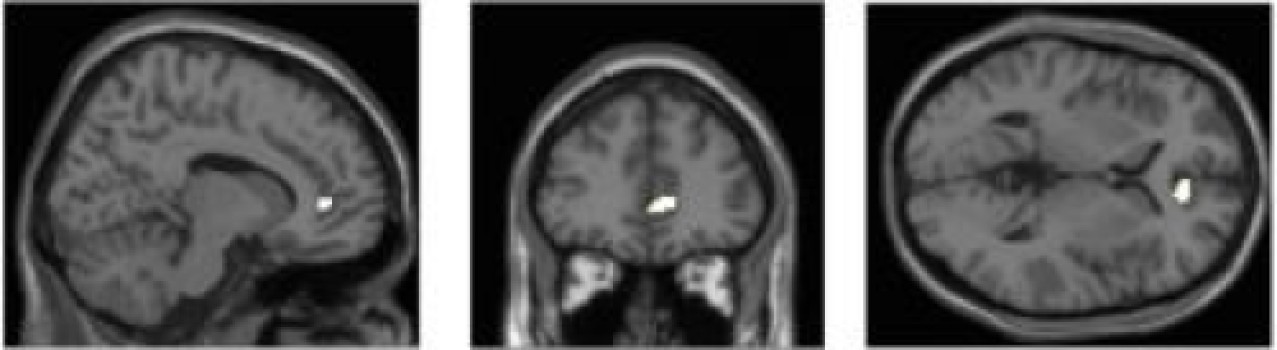

La densidad de materia gris en el córtex del cíngulo anterior está relacionada con la exposición a múltiples dispositivos multimedia. Fuente: Universidad de Sussex.

Los investigadores del Centro Sackler para la Ciencia de la Conciencia, de la Universidad de Sussex, utilizaron imágenes de resonancia magnética funcional (fMRI) para observar las estructuras cerebrales de 75 adultos, todos los cuales habían respondido un cuestionario sobre su uso y consumo de dispositivos multimedia, incluyendo teléfonos móviles y ordenadores, así como prensa de papel y televisión.

Observaron que, independientemente de los rasgos de personalidad individuales, las personas que utilizan un mayor número de dispositivos de este tipo al mismo tiempo tenían también menor densidad de materia gris en la parte del cerebro conocida como córtex del cíngulo anterior (CCA), región especialmente responsable de las funciones de control cognitivo y emocional.